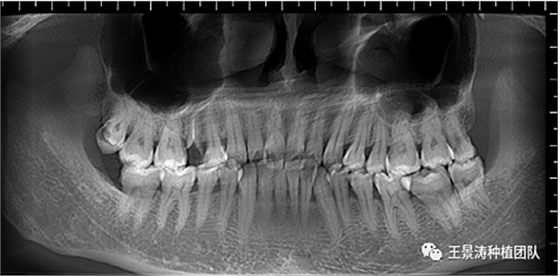

下述病例則是15區(qū)域的即刻種植,15因牙冠折斷于齦下,無法樁核冠修復(fù),則考慮種植修復(fù)。但拍攝CBCT后發(fā)現(xiàn)根尖距上頜竇底距離較短。患者為年輕女性,無全身系統(tǒng)疾病且可利用上頜竇底與根尖皮質(zhì)骨雙側(cè)皮質(zhì)骨固位,且此位置可通過頰側(cè)軟組織減張技術(shù)獲得嚴(yán)密封閉牙槽窩。因其根尖距上頜竇距離較低,遂拔除15后行上頜竇內(nèi)提升,埋入式種植,最終修復(fù)的完成。

左側(cè)下頜第二磨牙及右側(cè)下頜第一磨牙同時(shí)即刻種植病例?;颊吣贻p女性,無系統(tǒng)性疾病。37及46殘冠及殘根,且46劈裂,無法冠修復(fù),必須拔除。37根尖慢性炎癥,大量肉芽組織存在,46根分叉較高,根分叉骨質(zhì)尚可。CBCT示:根尖骨質(zhì)至下牙槽神經(jīng)管距離可滿足種植體的初期穩(wěn)定性,遂考慮即刻種植,并在種植體周邊填入骨粉并覆蓋骨膜,雙側(cè)的種植體初期穩(wěn)定性相差無幾,但考慮到37根尖慢性炎癥較大,遂給予埋入式種植。